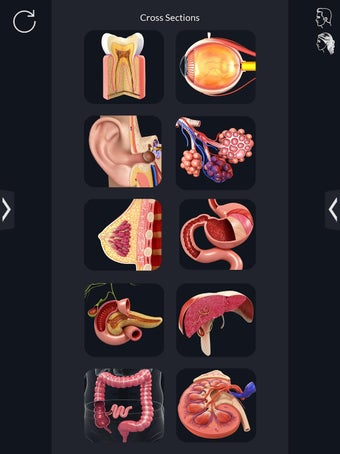

Met deze applicatie kun je 360° draaien rond een zeer realistisch 3D-model van het menselijk lichaam. Je kunt in- en uitzoomen op elk deel om er beter naar te kijken.

Je kunt alle informatie over de organen krijgen, inclusief hun locatie, hun functie en hoe ze eruitzien.